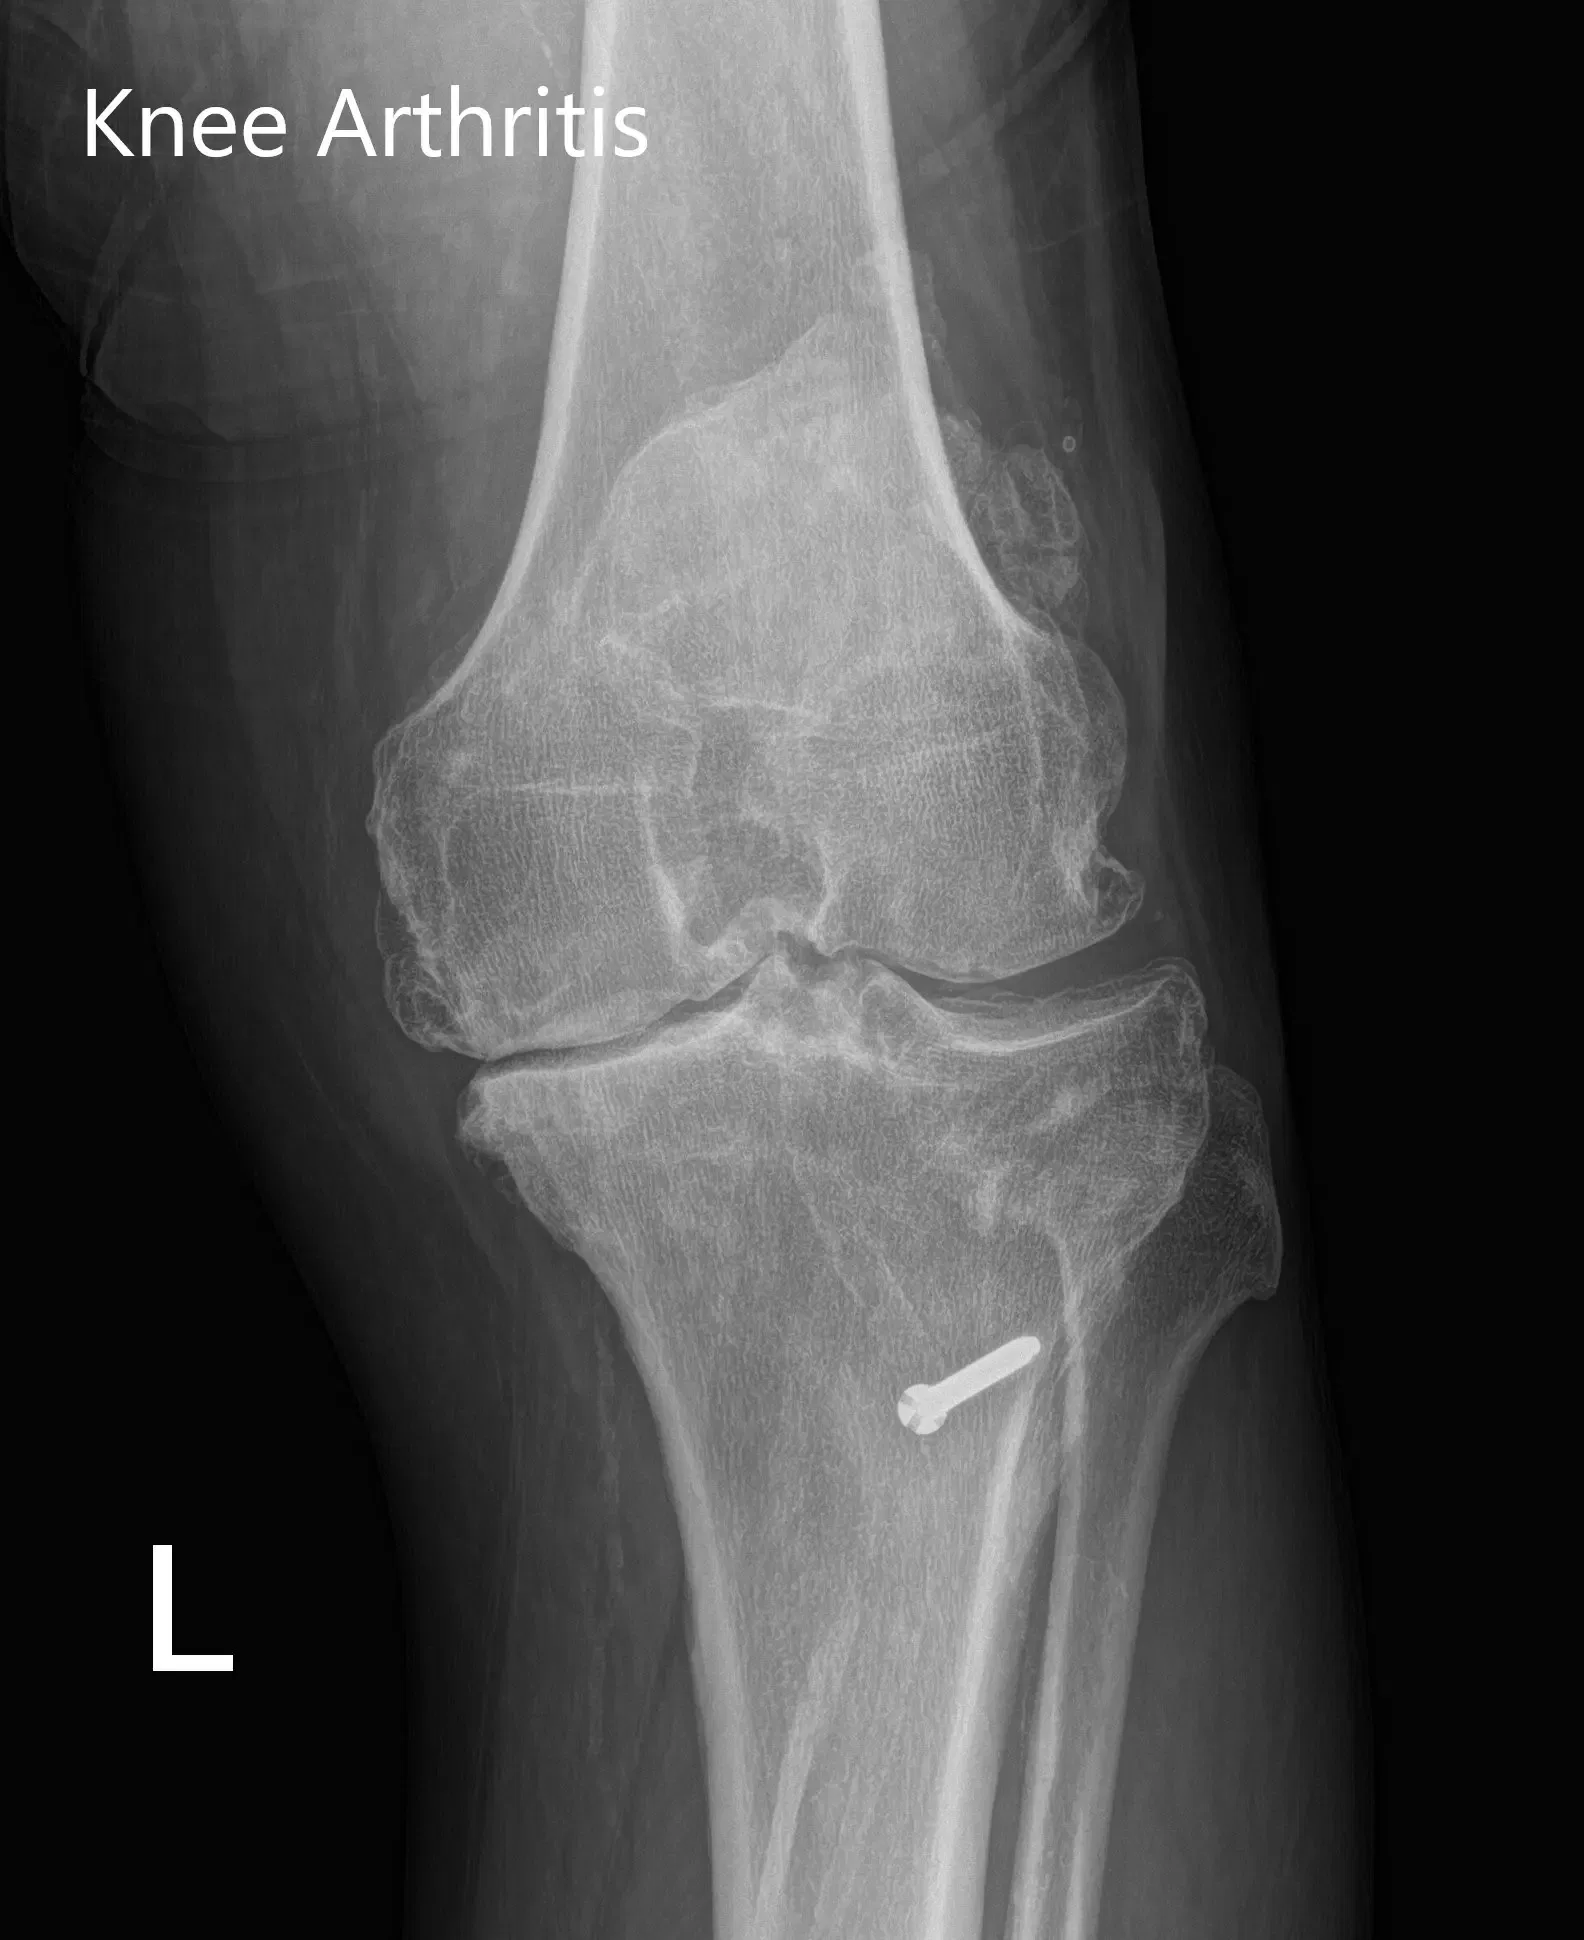

Her imaging studies revealed tricompartmental osteoarthritis of the left knee with a retained hardware (bolt) in the left proximal tibia. After assessing her medical conditions and physical examination she was deemed as a candidate for custom knee replacement. She was advised to undergo only the left side in view of the previous history of myocardial infraction and then proceed for right knee.

Preoperative X-ray of the left knee showing AP and lateral views with degenerative osteoarthritic changes and retained hardware in the proximal tibia.